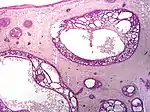

| Cystic basal-cell carcinoma | Morphologically characterized by dome-shaped, blue-gray cystic nodules.[23]:647 | ![]() | |

| Micronodular basal-cell carcinoma | Small and closely spaced nests. | ![]() | |